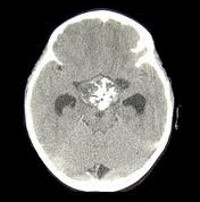

Важное диагностическое значение при пангипопитуитаризме имеют наличие гипохромной и нормохромной анемии, иногда лейкопении с эозинофилией и лимфоцитозом, низкого уровня глюкозы и повышенного содержания холестерина в крови. Для визуализации структурных аномалий гипофизарно-гипоталамической области при пангипопитуитаризме выполняют МРТ или КТ, позитронную эмиссионную томографию (ПЭТ) головного мозга, конусную боковую краниографию турецкого седла, для выявления сосудистых аномалий или аневризм - церебральную ангиографию. Также показаны рентгенография органов грудной клетки, черепа, позвоночника, костей рук для определения костного возраста у детей и наличия явлений остеопороза у взрослых, исследование полей зрения.